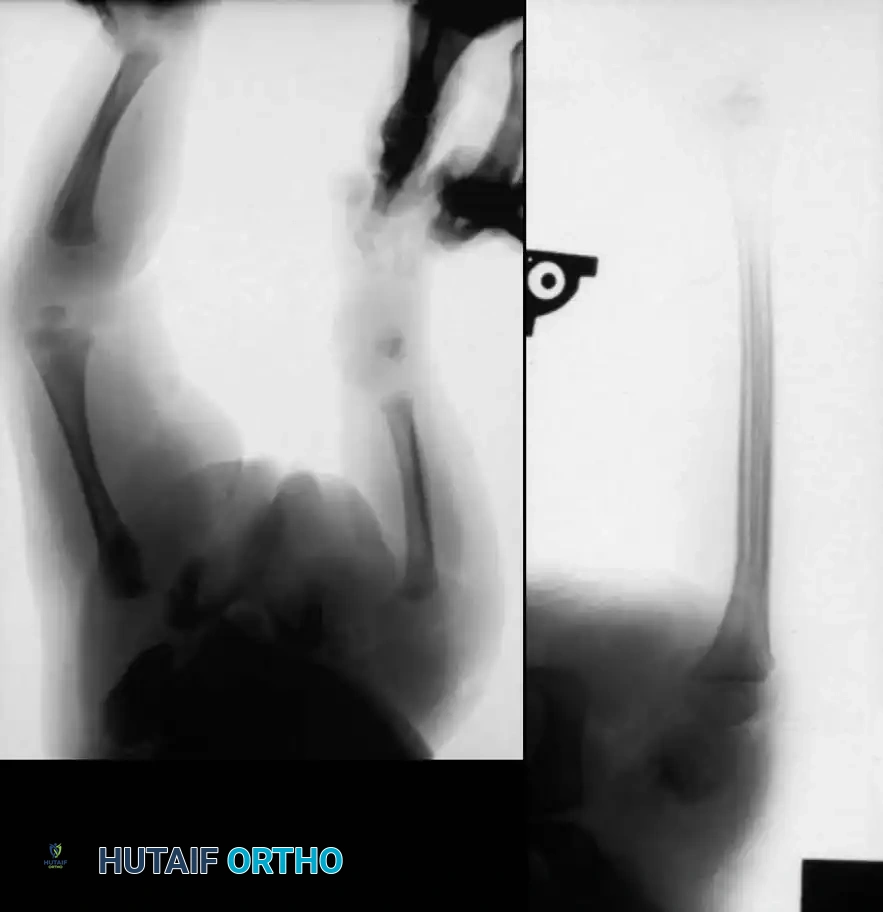

Proximal Tibiofibular Synostosis

For Type 1B and Type 2 tibial hemimelia, centralizing the mechanical axis is critical. The fibula must be brought under the mechanical axis of the femur or the existing proximal tibial anlage.

Technique Overview:

1. A lateral or anterolateral approach is utilized to expose the proximal fibula and the tibial anlage.

2. The proximal fibula is carefully osteotomized or mobilized, taking extreme care to protect the common peroneal nerve, which often has an anomalous course in these patients.

3. The cartilaginous tibial anlage is split or prepared to receive the proximal fibula.

4. The fibula is centralized beneath the tibia/anlage and fixed using smooth Kirschner wires or a small fragment plate, depending on the child's age and bone quality.

5. Bone graft (autograft or allograft) is packed around the synostosis site to promote rapid union.

By fusing the fibula to the tibia, the surgeon prevents the progressive lateral bowing and hypertrophy of the fibula that inevitably occurs if it is left in its native, eccentric position. This synostosis provides a robust, centralized bony column that can later be lengthened or fitted with a prosthesis following a distal Syme amputation.